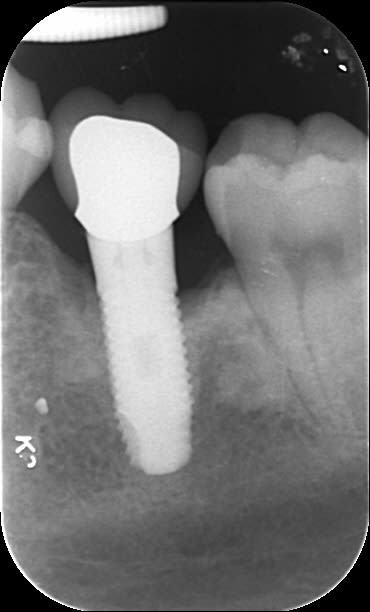

Et une idée pour celui là?

Un zimmer screw-vent 4.7?

Oui le deuxième est un tsv

L'autre la retro mal orientée ne me donne pas assez de détails....donc pas trouvé pour l'instant